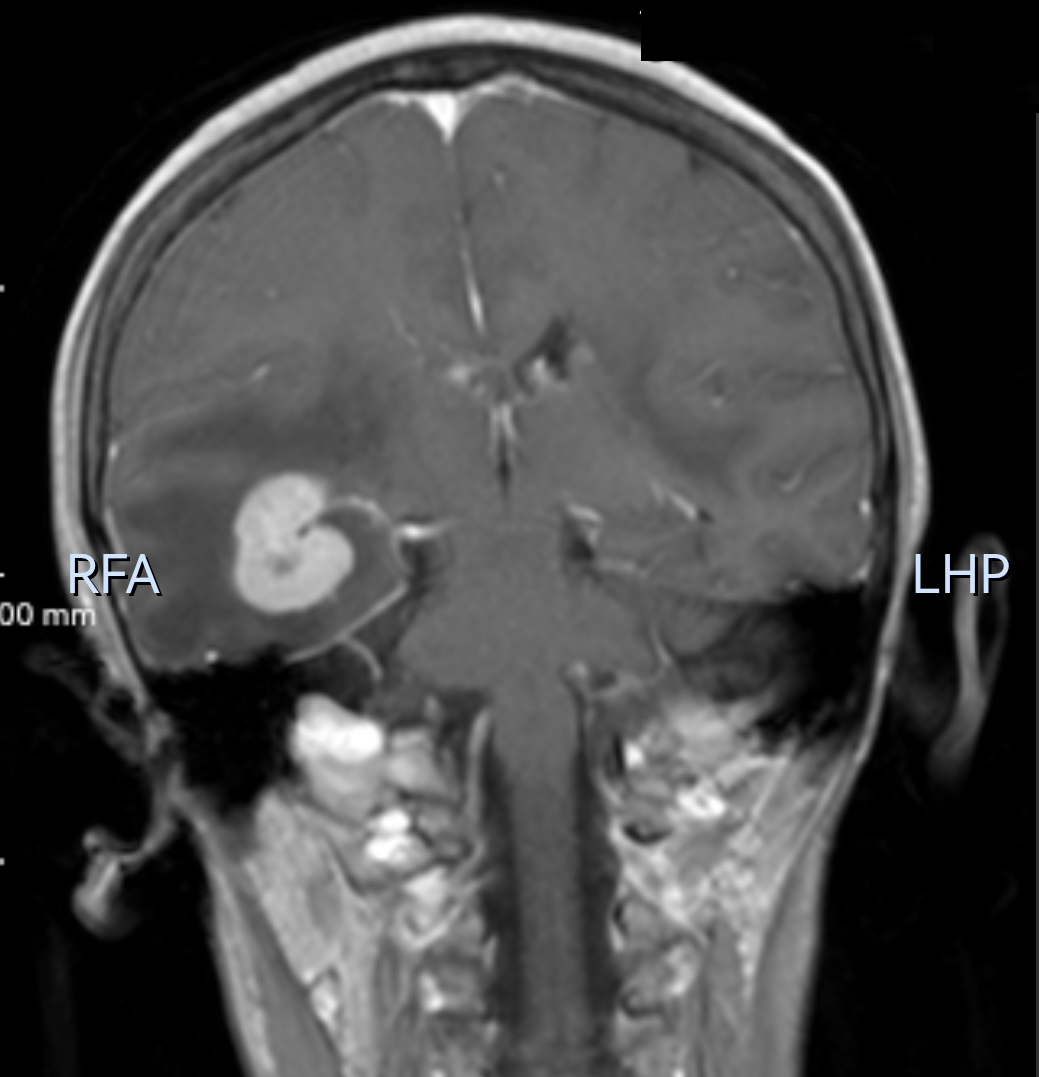

61岁的患者王女士因头痛10余天就诊外院,经头颅核磁共振检查显示颅内多发结节状占位,分布于双侧大脑半球及基底节区等部位,呈结节样强化,周围伴有明显水肿带。上述的描述与常见的“颅内多发转移瘤”(如肺癌、乳腺癌等实体瘤转移至脑部)高度相似,外院初步诊断为转移瘤,建议进一步寻找原发肿瘤灶。

为明确原发灶及病变性质,王女士来到贵州医科大学附属肿瘤医院进行了全身PET-CT检查,结果呈现几点特征:颅内多发结节代谢显著增高,较大的结节位于右侧颞叶,大小约3.2*2.1cm,且病灶周围水肿区的代谢相对较低,这很符合中枢神经系统淋巴瘤的表现。全身其他部位未见明确高代谢肿瘤灶,包括常见转移部位如肺、肝、骨等,因此基本排除实体瘤转移的可能。中枢神经系统淋巴瘤虽影像上常表现为“多发占位+水肿”,但其代谢活性通常更均匀且显著(因淋巴瘤细胞增殖活跃,葡萄糖代谢极高),而转移瘤水肿区代谢增高(因炎性反应),且多能找到原发肿瘤,因此,结合PET-CT全身无原发灶的证据,最终诊断为“原发性中枢神经系统淋巴瘤”。

患者经后续的颅内病灶立体定向活检,其病理结果证实为“弥漫大B细胞淋巴瘤(原发中枢神经系统)”,与PET-CT诊断完全一致。目前患者已在该院淋巴瘤科进行专科治疗,疗效显著。